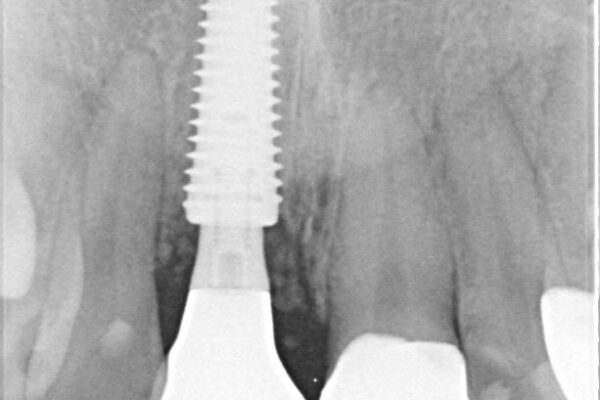

治療途中

• 「抜歯してブリッジ」と言われた20代女性が選んだ治療とは|たった4か月で自然な笑顔に抜歯即時インプラント+審美補綴の症例 治療途中画像